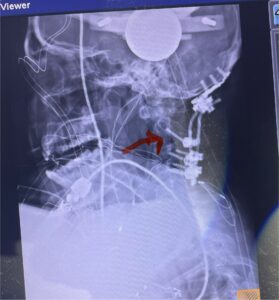

Cervical x-rays revealed a significantly increased atlanto-axial interval (Fig. 5) On review of her imaging studies it was noted that the right C2 isthmus was very thinned by the vertebral foramen (Figs 6a, b, and c) which would make an attempt at placing a C2 pars screw dangerous. A decision was made to perform an occipital-cervical fusion because only possible unilateral fixation and an extensive C1 laminectomy to be performed eliminating a fixation point if a more traditional C1-C2 was performed. Even if C1 lateral mass screws were able to be placed one could only perform a unilateral screw construct fixation to C2. We performed an occipital cervical fusion down to C4 to get enough inferior fixation and C1 laminectomy. The decompression went well. We placed a left unilateral pars screw and bilateral C3 and C4 lateral mass screws. We placed three 12 mm screws in the midline keel (Fig. 7). Postoperatively the patient had all around improvement in her symptoms and did not qualify for rehab. Her post op films at 6 weeks (Fig. 8)

Fig. 5: Lateral cervical x-ray demonstrating widened atlanto-dens interval as a result of instability (red dash).